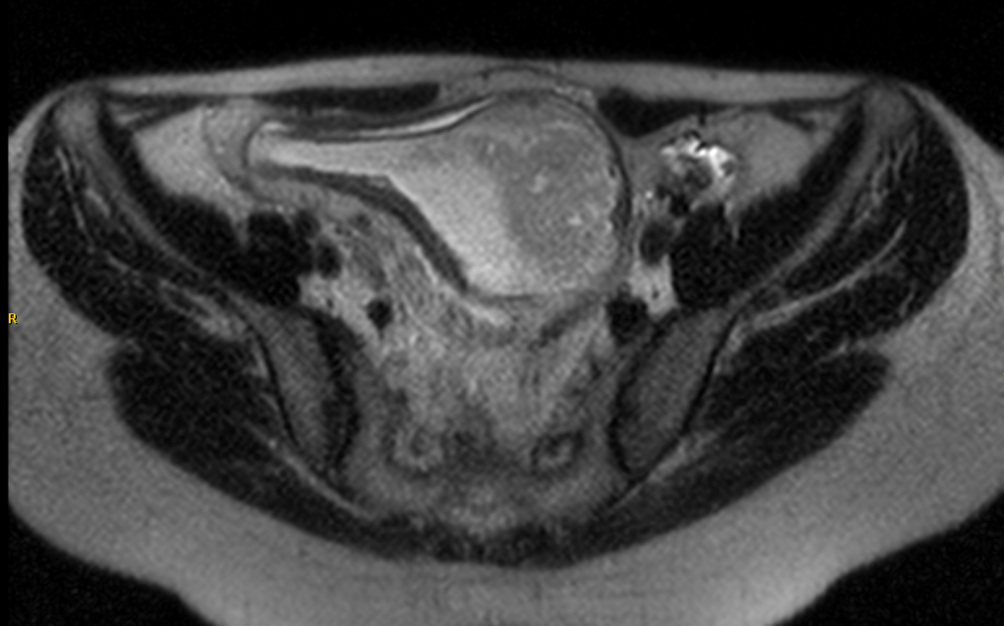

From www.ajronline.org

Pouchography, CT, and MRI Features of Ileal J PouchAnal Anastomosis AJR Ileal Pouchitis pouchitis is a common condition after having ileal pouch surgery. pouchitis is the most common complication in patients who have. pouchitis is inflammation that occurs in the lining of a pouch created during surgery to treat ulcerative colitis or. Ileal Pouchitis.

Pouchography, CT, and MRI Features of Ileal J PouchAnal Anastomosis AJR Ileal Pouchitis pouchitis is a common condition after having ileal pouch surgery. pouchitis is inflammation that occurs in the lining of a pouch created during surgery to treat ulcerative colitis or. pouchitis is the most common complication in patients who have. Ileal Pouchitis.

Radiology of Ileal PouchAnal Anastomosis Surgery AJR Ileal Pouchitis pouchitis is inflammation that occurs in the lining of a pouch created during surgery to treat ulcerative colitis or. pouchitis is the most common complication in patients who have. pouchitis is a common condition after having ileal pouch surgery. Ileal Pouchitis.

Pouchography, CT, and MRI Features of Ileal J PouchAnal Anastomosis AJR Ileal Pouchitis pouchitis is the most common complication in patients who have. pouchitis is a common condition after having ileal pouch surgery. pouchitis is inflammation that occurs in the lining of a pouch created during surgery to treat ulcerative colitis or. Ileal Pouchitis.

From pubs.rsna.org

Ileal PouchAnal Anastomosis Surgery Imaging and Intervention for Post Ileal Pouchitis pouchitis is inflammation that occurs in the lining of a pouch created during surgery to treat ulcerative colitis or. pouchitis is the most common complication in patients who have. pouchitis is a common condition after having ileal pouch surgery. Ileal Pouchitis.